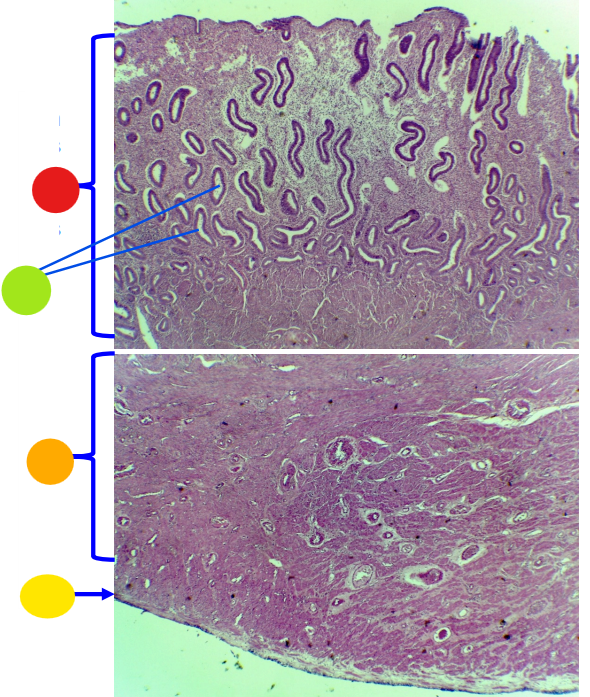

red

tunica albuginea

orange

primordial follicles

red

primary follicle

orange

secondary follicles

what is this

tertiary follicle